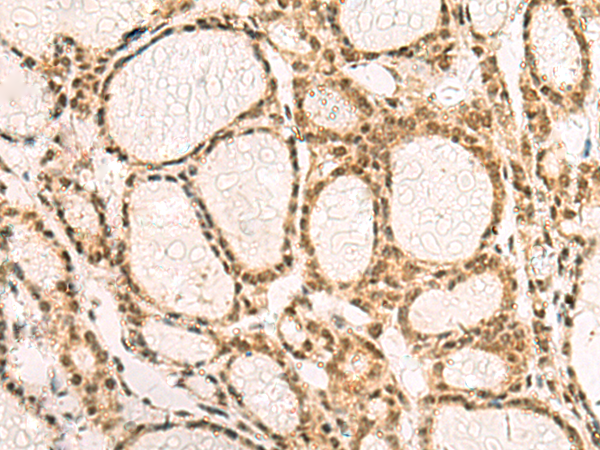

分类: 科研抗体货号: P07404别名: UKLF应用: IHC反应种属: Human